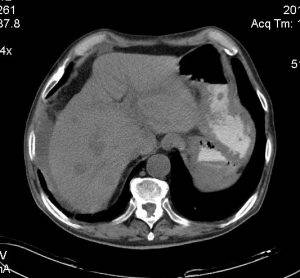

Фото метастазов печени

Для выявления печеночных метастазов используются специальные функциональные тесты. Также весьма информативно ультразвуковое исследование, но спиральная компьютерная томография с контрастированием гораздо показательнее.

К инструментальным методам диагностики относят УЗИ, КТ или МРТ, сцинтиографию органа. Метастазы в печень диагностируются как наличие маленьких солитарных депозитов. Признаки метастаза печени удобнее распознать на КТ, на снимке орган выглядит как большая узловатая поверхность (не нужно путать с циррозом).